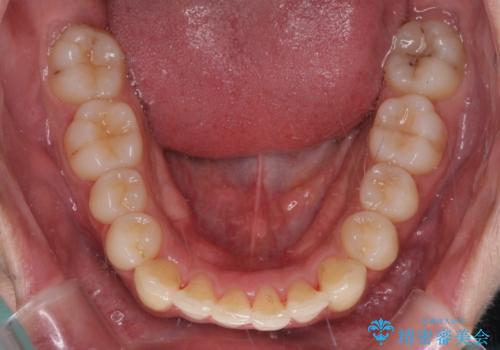

- 矯正治療の後戻りを気にして来院された患者様です。

後戻りは軽微であったので、インビザライン・ライトにより矯正治療を行うこととしました。

インビザライン・ライトは提供されるマウスピースの数に制限があり、通常のタイプよりもマウスピース提供期間が短くなっている一方、安価に治療を行うことができるプランです。

治療のゴールも変更できないため、軽微な歯列不正や、後戻り改善などに適しています。